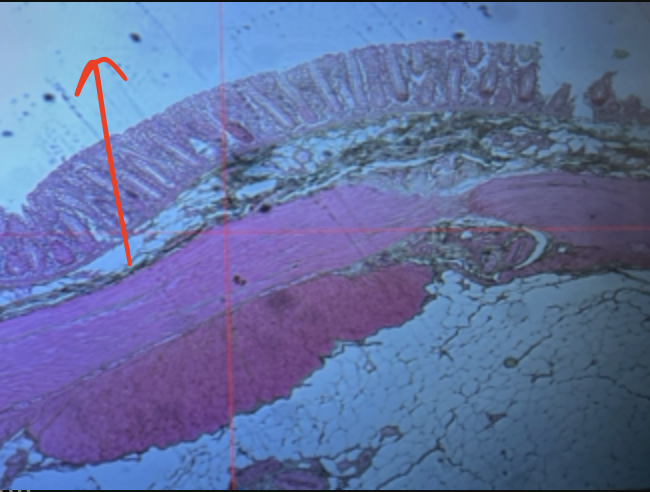

jejunum

villi

intestinal crypts

lumen

mucosa

mucosal epithelium

lamina propria

muscularis mucosa

submucosa

muscularis (externa)

serosa/adventitia